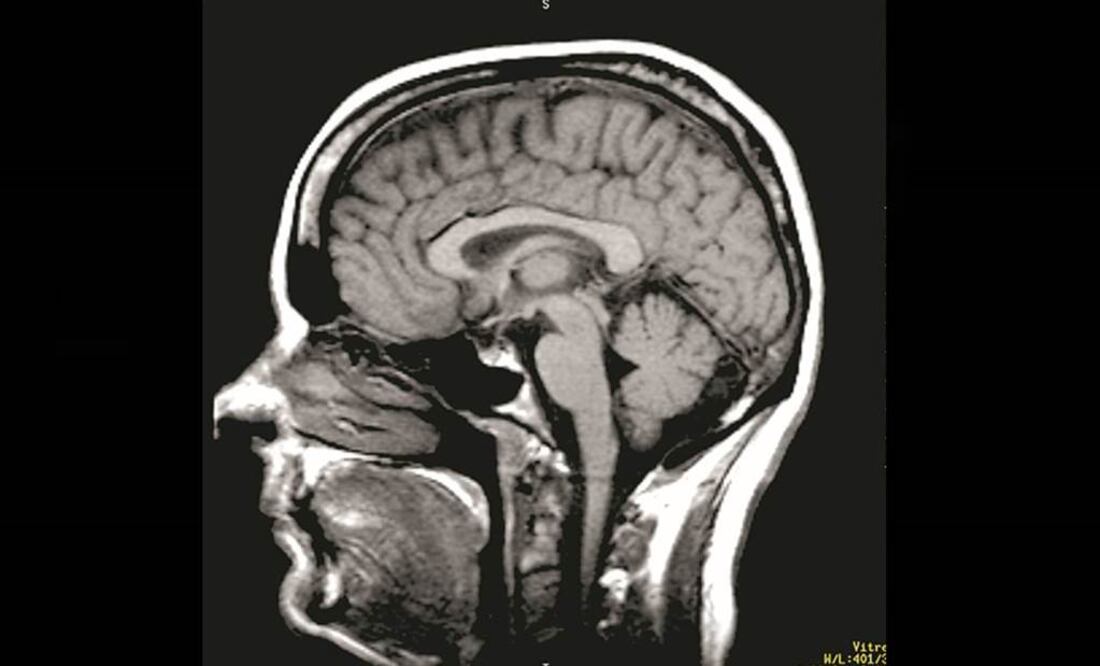

Un ruso aquejado de atrofia muscular espinal(AME), una grave enfermedad genética que ataca las neuronas motoras, quiere someterse a una pionera operación en la que su cabeza sería trasplantada a un cuerpo sano uniéndola por la espina dorsal.

Según informan varios medios rusos, el programador Valeri Spiridónov se puso en contacto con el controvertido doctor italiano Sergio Canavero, quien cree que es técnicamente posible realizar la operación en 2016.

Canavero quiere reunir a un equipo de 150 doctores y enfermeras para llevar a cabo la cirugía, que se estima costaría algo más de 10,3 millones de euros.

El único precedente de una operación similar se produjo en 1970, cuando el doctor Robert White, de la Universidad de Medicina Case Western Reserve, trasplantó la cabeza de un simio al cuerpo de otro. Ocho días después, el animal murió.